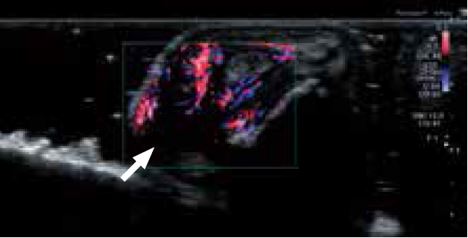

Виключення можливості розвитку атрезії жовчовивідних шляхів

Діагностика атрезії жовчовивідних шляхів у дітей є складним завданням, проте це одне з найважливіших клінічних застосувань ультразвукової візуалізації. Існує чотири основні типи атрезії жовчовивідних шляхів, але майже всі типи можна виключити, якщо підтвердити прохідність жовчної протоки від портального отвору печінки до загальної жовчної протоки. Оскільки діаметр дитячої жовчної протоки становить приблизно 1 мм (стрілка), визначити її прохідність за допомогою звичайних датчиків надзвичайно складно. За допомогою нового надвисокочастотного датчика можна підтвердити прохідність позапечінкової жовчної протоки і, відповідно, з упевненістю виключити атрезію жовчовивідних шляхів ( мал. 7). Нове покоління датчиків Aplio i-серії дозволяє збільшити клінічну достовірність діагнозу та уникнути додаткових інвазивних діагностичних процедур.

Малюнок 7. Дослідження жовчовивідних шляхів у дитини з підозрою на атрезію жовчовивідних шляхів за допомогою PLI-2004BX (24 МГц).